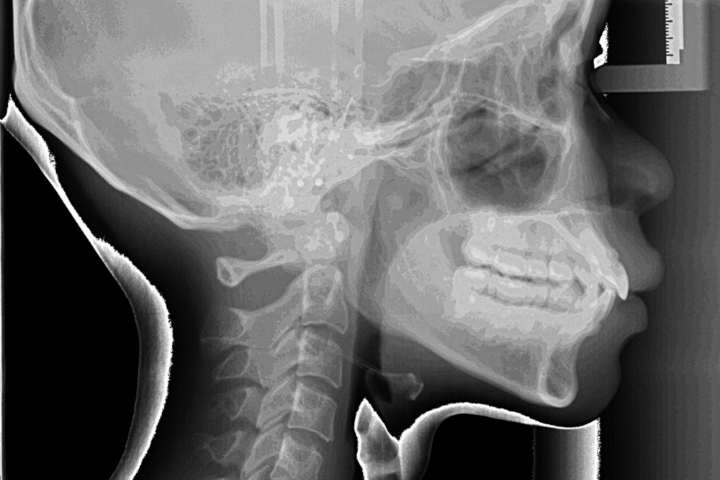

セファロ写真(横顔のレントゲン)や歯型を分析し、それぞれにあった治療プランをご提案致します。

矯正治療で大切なセファロ写真